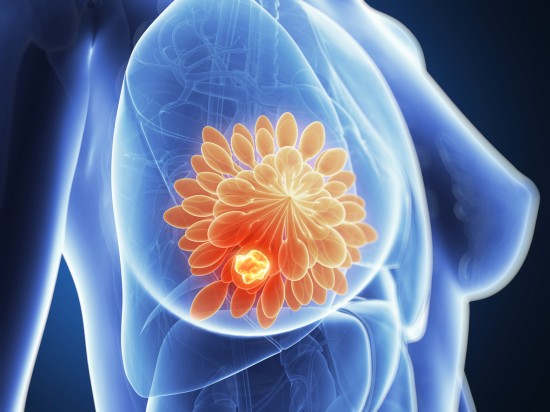

| Crean dispositivo que predice cáncer de mama 5 años antes de que aparezca. | ||||||

| Los investigadores del MIT crearon un modelo basado en inteligencia artificial que es capaz de detectar oportunamente este tipo de cáncer en todas las mujeres | ||||||

Tan solo en México esta enfermedad es la más diagnosticada entre las mujeres. Por si fuera poco, es la principal causa de mortalidad por tumores malignos en damas a partir de los 20 años. Afortunadamente, ya existe una manera de detectarlo a tiempo porque científicos del MIT han creado un dispositivo que predice el cáncer de mamá hasta 5 años antes de que aparezca. De acuerdo con la Organización Mundial de la Salud (OMS), el cáncer de mama es uno de los más comunes y agresivos que existen en el mundo . Por esta razón, es recomendable que cada mes realices una autoexploración en tus senos para detectar hundimientos, enrojecimiento, bultos o cualquier otro tipo de cambio. ¡Tú te conoces mejor que nadie! En esta nota te decimos cuáles son los síntomas del cáncer de mamá. Los investigadores del Massachusetts Institute of Technology crearon un modelo basado en inteligencia artificial que es capaz de detectar oportunamente este tipo de cáncer en todas las mujeres, sin importar su tipo de piel. Es importante enfatizar el color de piel porque, de acuerdo con el MIT, las mujeres con piel oscura tienen un 42 por ciento más de probabilidades de fallecer a causa del cáncer de mama que las mujeres blancas. ¿Cómo funciona este dispositivo? Los científicos se basaron en la información de más de 90 mil mamografías que fueron realizadas a pacientes con cáncer de mama, buscaron los patrones comunes en el tejido mamario y crearon un dispositivo que es capaz de reconocerlos y encontrar potenciales tumores malignos para ganar tiempo en la lucha contra esta enfermedad mortal. Los investigadores aseguran que esta herramienta reconoce los patrones sin importar el historial genético del paciente, así como su peso, si está lactando o el tipo de dieta que tiene. Sin duda es un avance importante para la salud porque hasta ahora nadie había creado este tipo de sistema que ayudará a salvar muchas vidas. Cabe mencionar que no es un dispositivo que esté a la venta, sino que está destinado para que el sector salud arme un programa de detección oportuna y lo aplique adecuadamente en los chequeos de rutina para así evitar el trágico diagnóstico tardío. Conocer tus senos es de vital importancia, no dudes en realizar la autoexploración y tócate para que no seas parte de las estadísticas. ¡Podrías salvar tu vida! |